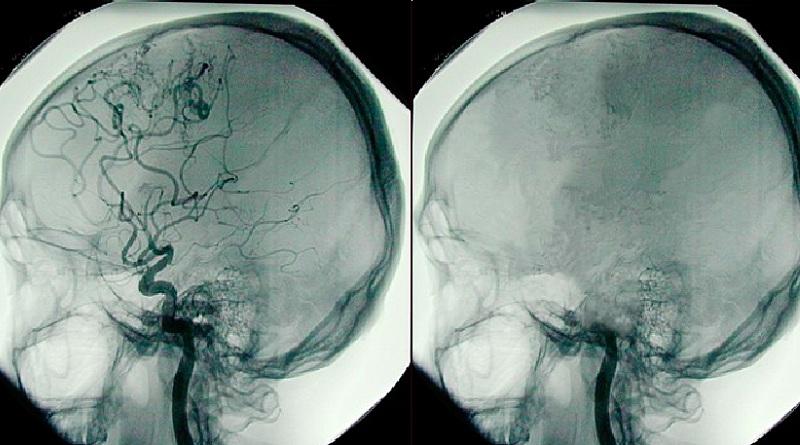

BEYİN ÖLÜMÜ TANISI

Beyincik ve beyin sapının geri dönülemez bir şekilde kaybolduğu beyin ölümünde bu tanımlamada ufak bir şüphe olmamalıdır. Yani uzman doktorlar bu kararı alırken yüzde yüz emin olmalıdır. Beyin ölümünün tam anlamıyla gerçekleştiği kararına 4 uzman karar vermektedir. Bu 4 uzmanın kendine ait ayrı ayrı testleri vardır.

Peki, kimdir bu uzmanlar: Anestezi uzmanı, Nöroloji uzmanı, Nöroşirürji uzmanı ve Kardiyoloji uzmanı. Bu uzmanlar kendi alanlarında gerekli testleri yaparak ortak bir karar alırsa beyin ölümü tanısı konur. Eğer uzmanlardan biri beyin ölümü tanısı için yüzde yüz emin değilse bütün işlemler durur.